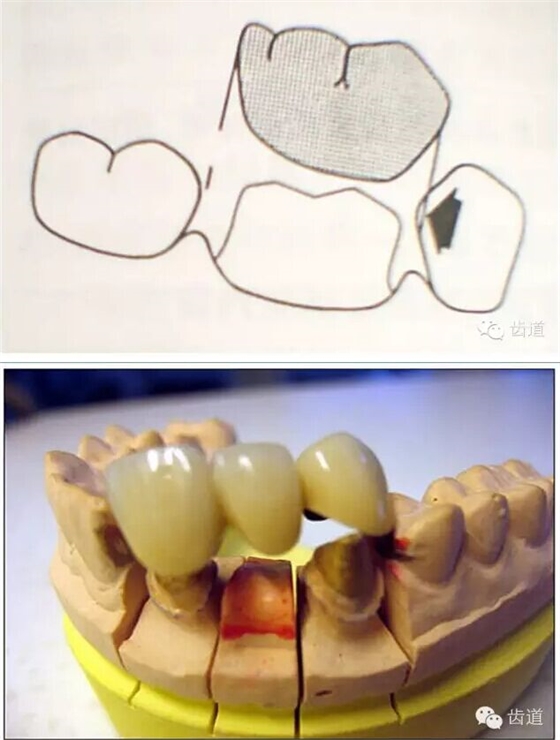

正壓力:即修復(fù)體的密貼程度(小于0.2mm)

表面粗糙程度

牙的外形及洞形的幾何形狀:主要是牙體制備出一定聚合角度產(chǎn)生的阻擋作用